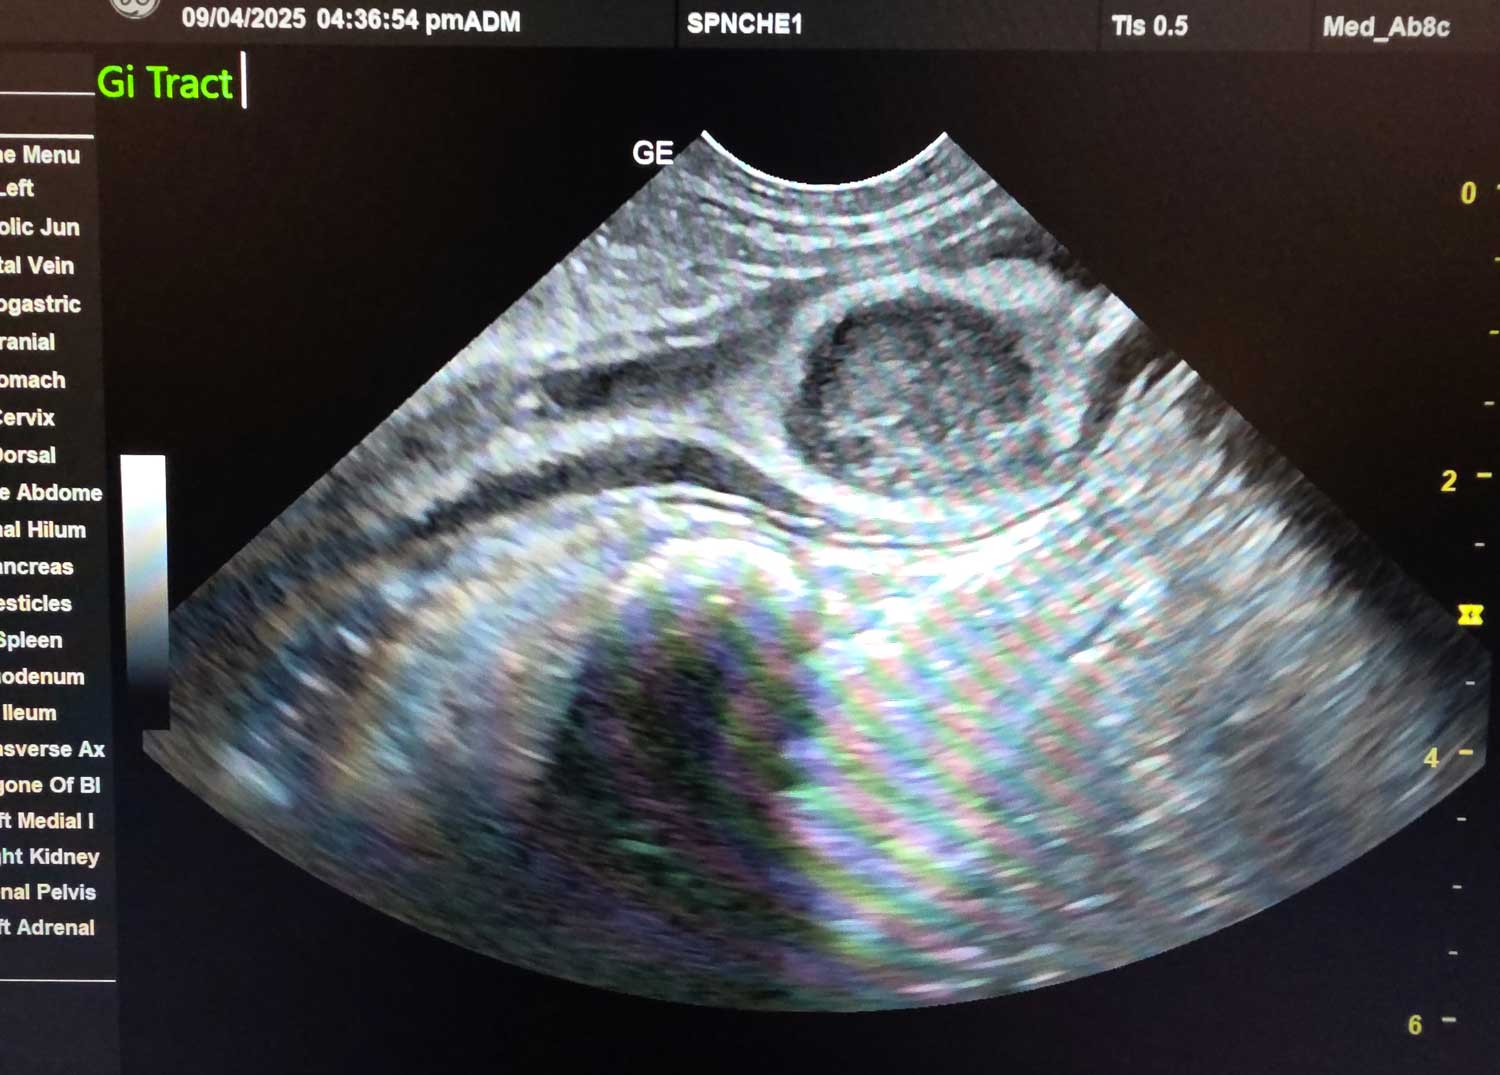

Canyon Falls is excited to offer in-house diagnostic abdominal ultrasound. Ultrasound, or sonogram, uses high-frequency sound waves to provide images of your pet’s internal organs. This non-invasive, painless test is crucial for diagnosing many different diseases.

Unlike x-ray, which shows the outside shape/size of the organs, ultrasound gives images of the inside of those organs. Together, this comprehensive view helps to rule out certain conditions and get a definitive diagnosis for many. With this tool we can see the inside of the liver, gall bladder, kidneys, spleen, stomach/intestines, urinary bladder, adrenal glands, lymph nodes and pancreas.

Using this advanced device we can investigate for causes of vomiting, diarrhea, pain, changes in appetite or thirst, weight loss, infection, and to explore for tumors, abscesses and foreign material among other findings.